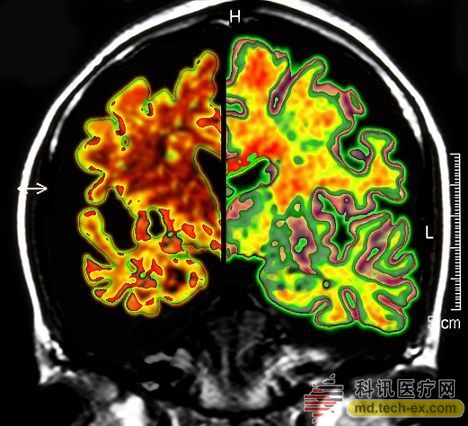

在手術中,所有病患的腦部將被植入電極,這些電極與一個類似起搏器的裝置相連接,能夠每秒鐘發出130次電脈沖。羅森博格表示,病人并不會感受到電脈沖的存在。 研究人員表示,所有接受臨床試驗的病人同時都會被植入這個“起搏器”裝置。其中,一半病人的“起搏器”將于手術后兩周開啟,而另一半病人的要在手術后一年才會開啟。目前,參加臨床試驗的病人和醫生并不知道分組情況。 其實早在2010年,加拿大就已經對這種大腦“起搏器”展開臨床試驗。當時,有6名輕微老年癡呆癥患者參加。當時的試驗結果顯示,在13個月的觀察期中,這些病患的葡糖糖代謝速度持續上升,這也就說明他們的大腦神經元正在工作。而在同時期內,大部分老年癡呆癥患者的葡萄糖代謝水平則是在不斷下降。